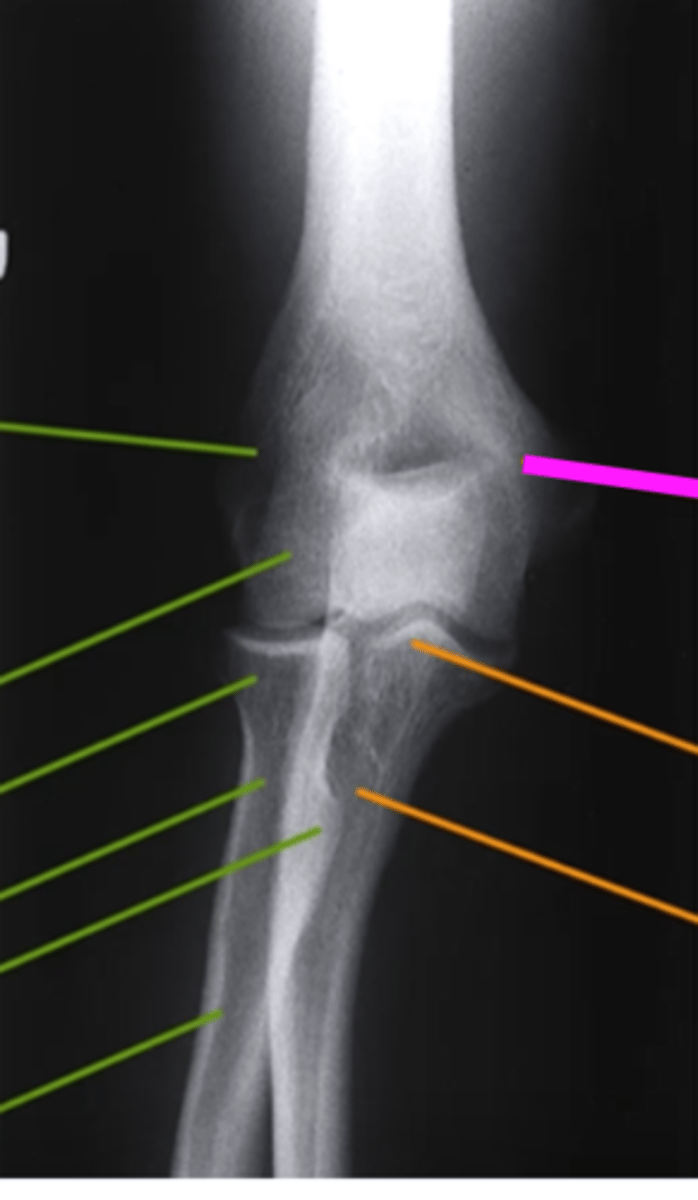

AP Elbow

what view is this

lateral epicondyle

what does the pink line point to?

medial epicondyle

Capitulum

coronoid process

shaft of ulna

shaft of the radius

radial tuberosity

radial head

radial neck